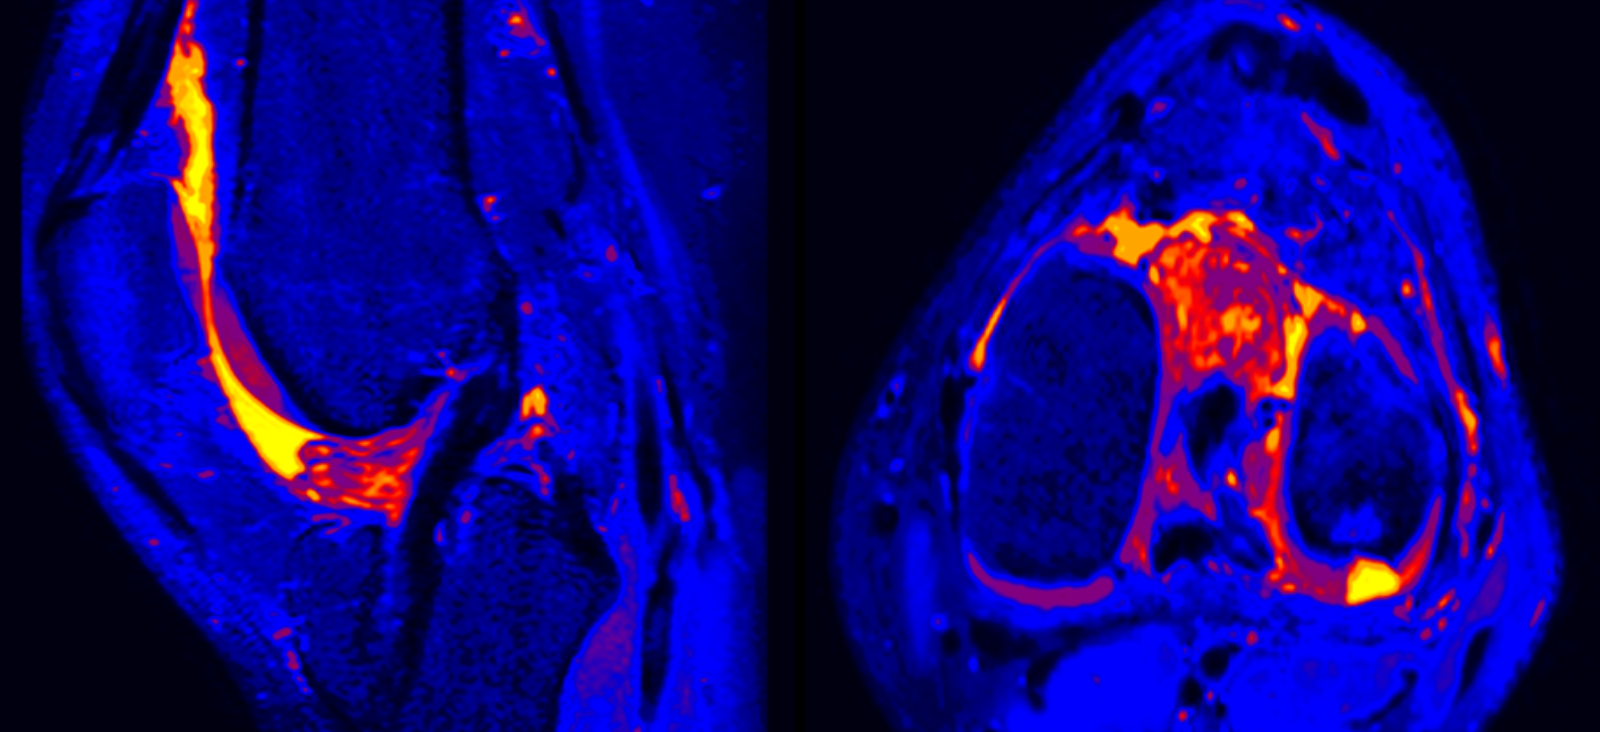

Dr. Chhabra is the Chief of Musculoskeletal Radiology at UT Southwestern and a leading expert in the use of 3D imaging for sports injuries, functional imaging of bone and soft-tissue tumors, image guided interventions, and magnetic resonance neurography (MRN) to map peripheral neuropathy and direct perineural nerve injections.